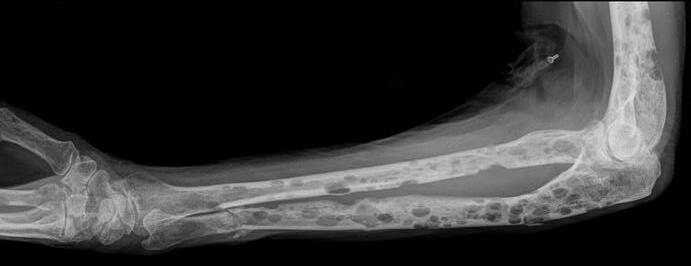

Conventional X-rays reveal punched-out lytic lesions, osteoporosis, or fractures in 75% of patients.

FDG PET/CT appears to be more sensitive (85%) than skeletal survey for the detection of small lytic bone lesions.

Multiple Myeloma •

Kyle RA et al. Mayo Clin Proc Jan;78(1): 2003. Nanni Cet al. European Journal of Nuclear Medicine and Molecular Imaging Vol.33:2006 Dimopoulos MA, et al. Leukemia. 2009 • Diagnosis is confirmed with bone marrow demonstrating greater than 10% involvement by malignant plasma cells with either CRAB or SLiM Malignant Plasma cells seen on biopsy AND ≥1 “CRAB” feature OR have >1 SLiM ‘high risk” features: C: Calcium elevation(>11mg/dL) R: Renal- low kidneyfunction; (serumcreatinine >2mg/dL) A: Anemia –low redblood count (Hb <10 g/dL) B: Bone disease (≥1 lytic lesionson skeletalradiography, CT, or PET-CT) S: >60%PlasmaCells onBoneMarrow biopsy Li: Serumlightchainratio >100 M:>1 lytic lesionsonMRI (or PET/CT scan)